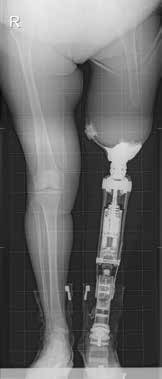

Bei der Durchführung des Indikationsverfahrens wird von den Autoren ein multidisziplinärer Teamansatz verfolgt. Das Behandlungsteam für die Osseointegration besteht aus einem orthopädischen Chirurgen, einem Fallmanager, einem Rehabilitationsmediziner und einem Physiotherapeuten. Patienten, die zur Implantation einer knochenverankerten Prothese überwiesen werden, werden vom Fallmanager in eine ambulante Gruppenklinik eingeladen. Vor ihrem Besuch füllen sie den Fragebogen für Personen mit einer transfemoralen Amputation (Q‑TFA) aus 1. In der ambulanten Gruppenklinik wird zunächst eine radiologische Untersuchung des verbleibenden Femurs bzw. der verbleibenden Tibia durchgeführt und eine kalibrierte Gesamtansicht der beiden unteren Extremitäten angefertigt (Abb. 1a). Bei Patienten mit Unterschenkelamputation oder mit kurzem Oberschenkelstumpf wird ein CT-Scan durchgeführt. Mit diesem CT-Scan werden die Größe und das Design des anzufertigenden kundenspezifischen Implantats ermittelt. Sämtliche Einzelheiten der Behandlung werden im Rahmen einer Plenarsitzung vom Chirurgen und vom Rehabilitationsmediziner vorgestellt, gefolgt von Einzelberatungen mit dem gesamten Osseointegrationsteam. Während der Einzelgespräche werden dem Rest der Kandidaten und ihren Angehörigen zwei Personen mit knochenverankerter Prothese vorgestellt, die ihre Rehabilitation erfolgreich abgeschlossen haben. Diese berichten den neuen Kandidaten von ihren Erfahrungen und zeigen ihnen ihre knochenverankerte Prothese. Abschließend wird ein gemeinsamer Konsens in Bezug auf die Indikation zur Behandlung auf Grundlage der Ein- und Ausschlusskriterien 2, der Krankengeschichte, der körperlichen Untersuchung, der Q‑TFA-Ergebnisse sowie der Radiographie erzielt. Kandidaten mit unrealistischen Erwartungen an ihre zukünftige Funktionsfähigkeit mit einer knochenverankerten Prothese werden an die klinischen Psychologen zum Gespräch überwiesen, um ihre Erwartungen zu korrigieren, die wahrscheinlich zu hoch sind.